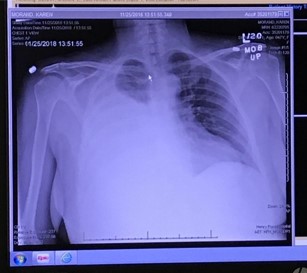

My belly didn’t swell up again, but a week later I was back in the hospital, having trouble breathing and chest pain. Even worse than the week prior. It turns out that the same fluid was now building up in my chest cavity instead of my belly. There wasn’t any extra room in there (since ribs don’t flex), so it was crushing my lungs.

This began what turned out to be a 26-day hospitalization – almost the entire time between Thanksgiving and Christmas. The transplant staff tried everything they could to make me healthy again. They started with putting in a long-term drain (called a chest tube) into my back, to remove the fluid and relieve all the pressure on my lungs. They added some extra medications to slow down my lymphatic system. After the low-fat diet proved ineffective, they switched me to TPN, which is where you get all your nutrition from an IV. I wasn’t allowed to eat or drink anything for almost 3 weeks, other than ice chips.